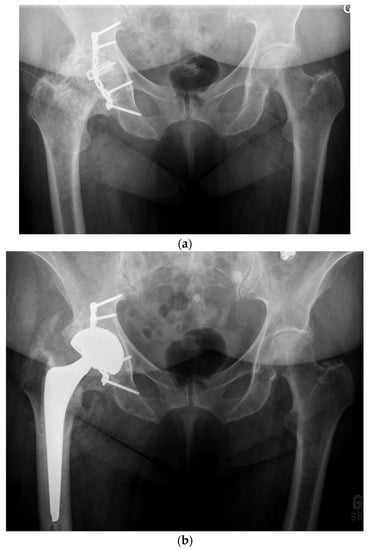

For the older, more sedentary patient or the patient with a shorter life expectancy, DM LDH THA is the ideal alternative (Figure 7 and Figure 8). DM implant design has the LDH stability benefits and wear rates significantly lower than fixed bearing implants [,]. Loving et al., in a simulator study, under multiple test conditions (impingement, abrasion, loss of mobility of the insert), showed that the performance in terms of wear was dictated mainly by the smaller articulation and by the polyethylene material used. For the most severe tests, a 75% lower wear rate was observed compared to a fixed insert of conventional polyethylene sterilized under gamma rays in an inert atmosphere []. Additionally, with osteopenic bone there is a higher risk of intra-operative periprosthetic fractures with LDH press fit monoblocks [,]. Bearing a lower cost and avoiding the potential drawbacks of hard-on-hard bearings (noise, fracture, and trunnionosis), DM should be considered for patients over 65 years.

Figure 8.

(a) Antero-posterior pelvis radiograph of an 82-year-old man with severe post-traumatic right hip osteoarthritis. The fracture and secondary degeneration modified native acetabular cavity orientation. Using a DM, LDH THA helped obtain a stable joint and may forgive potential surgical impressions. (b) Post-operative anteroposterior pelvis radiograph. (c) Lateral view of the reconstructed right hip.